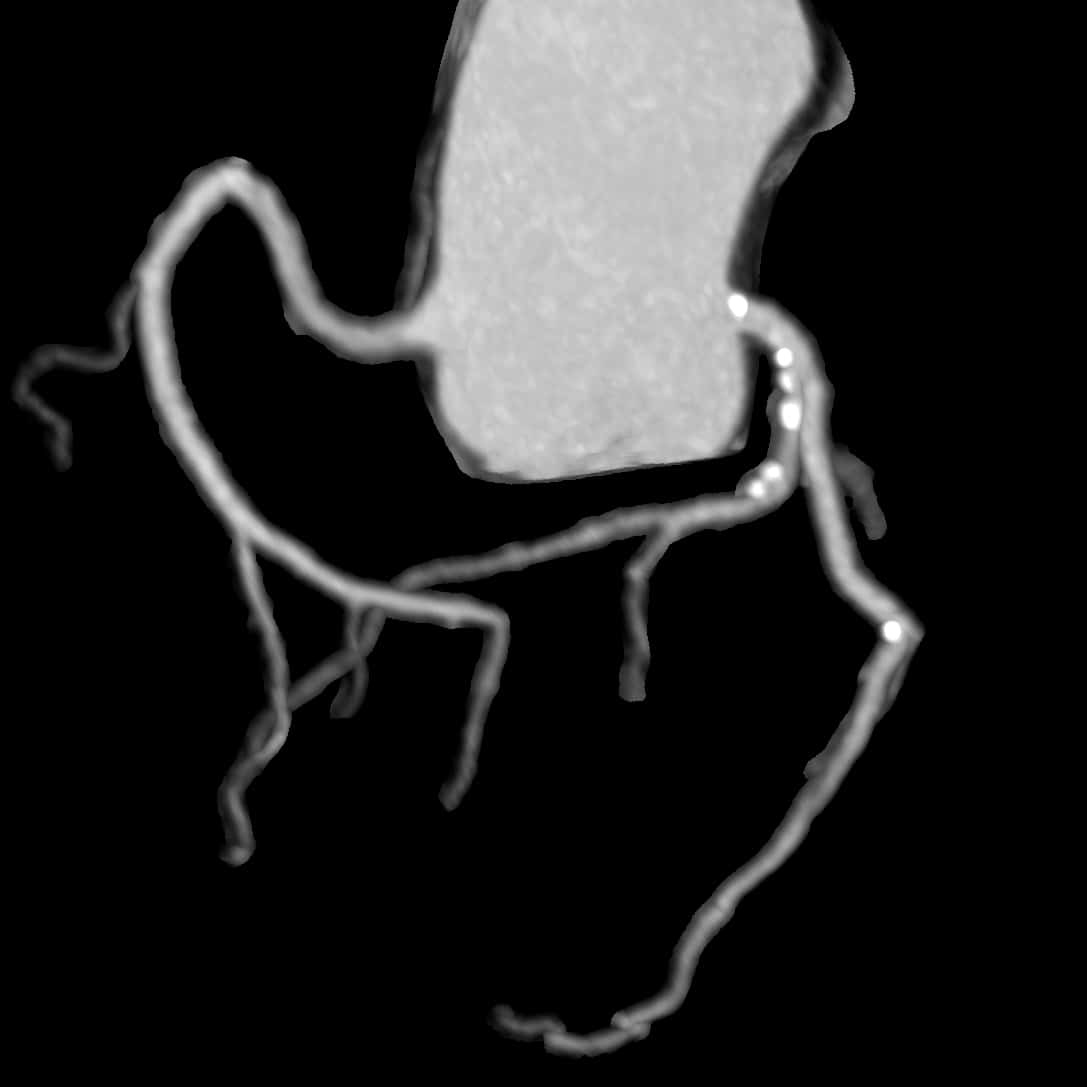

Die Herz-CT wird hĂ€ufig zur Beurteilung der HerzkranzgefĂ€Ăe eingesetzt, insbesondere zur AbklĂ€rung von Verkalkungen oder Verengungen (Koronare Herzerkrankung). Mit der CT-Angiographie lassen sich auch GefĂ€Ăe detailliert darstellen. Die Untersuchung dauert nur wenige Minuten, in den meisten FĂ€llen ist die Gabe eines Kontrastmittels erforderlich.